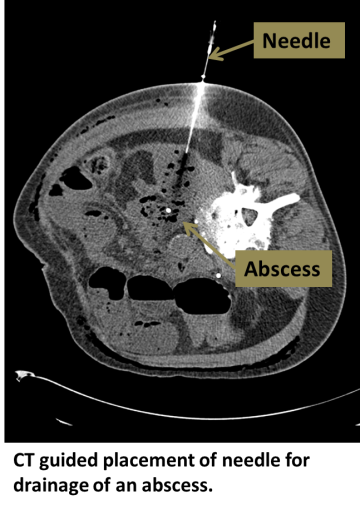

An interventional radiologist uses ultrasound or CT guidance to place a drain into the abnormal collection.